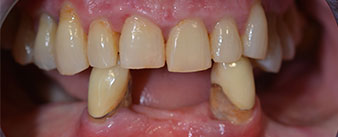

La paciente de 64 años se presentó con una dentición residual compuesta por las piezas dentales 38, 33 y 43 en el maxilar inferior y con una prótesis temporal fijada con ganchos en el maxilar inferior (figs. 1 y 2).

dentición residual

Fig. 1

Fig. 2